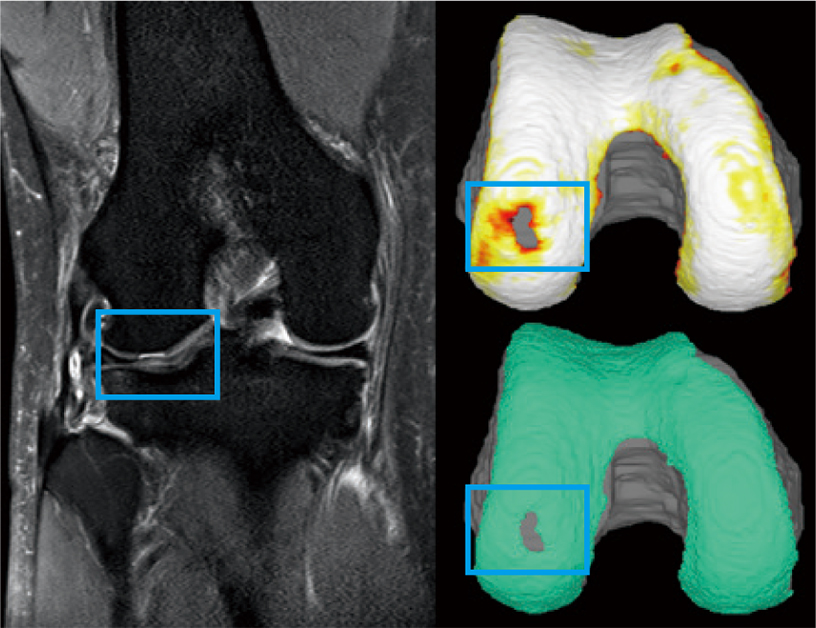

具体例を示す。症例C(図7)は、大腿骨外顆の軟骨部分欠損例である。

slice画像で軟骨欠損は理解できても全体的な軟骨欠損の大きさは理解しにくいが、3D構築することで、位置や大きさも理解しやすい。

図7:症例C